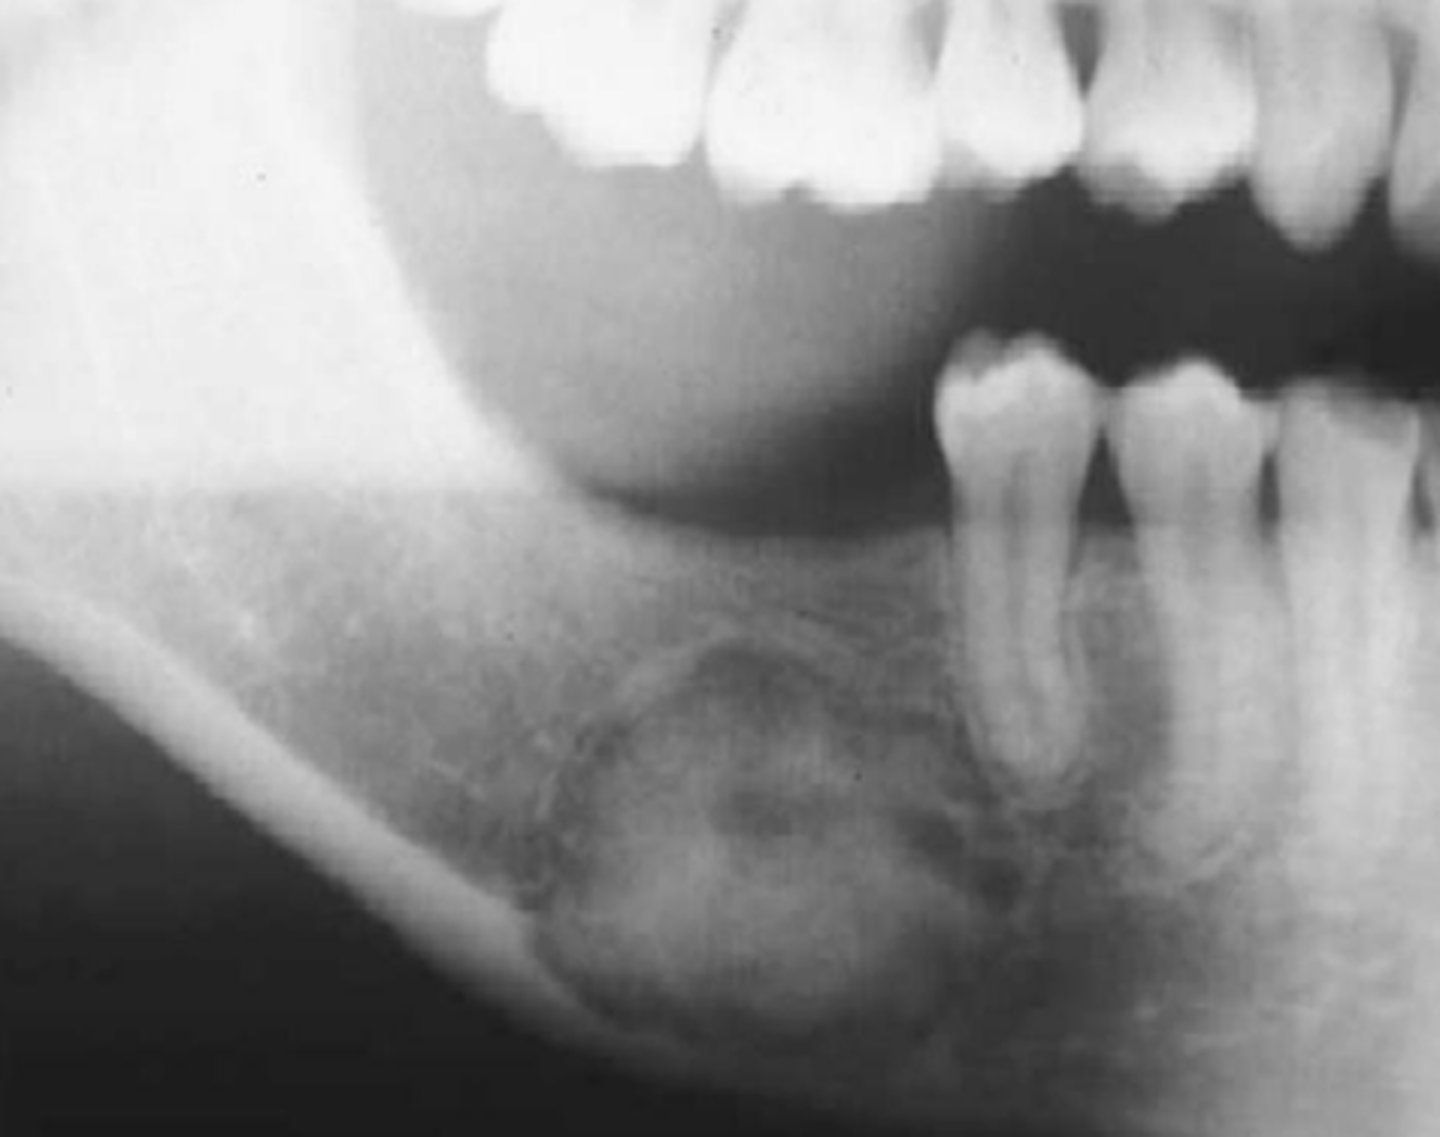

Central Giant Cell Granuloma

reactive lesion

multinucleated giant cells

What is a clinical feature of Central Giant Cell Granuloma?

purple overlying mucosa

Location of Central Giant Cell Granuloma

mandible

Periphery of Central Giant Cell Granuloma

well defined RL margin

Internal Structure of Central Giant Cell Granuloma

RL, granular pattern, wispy septae